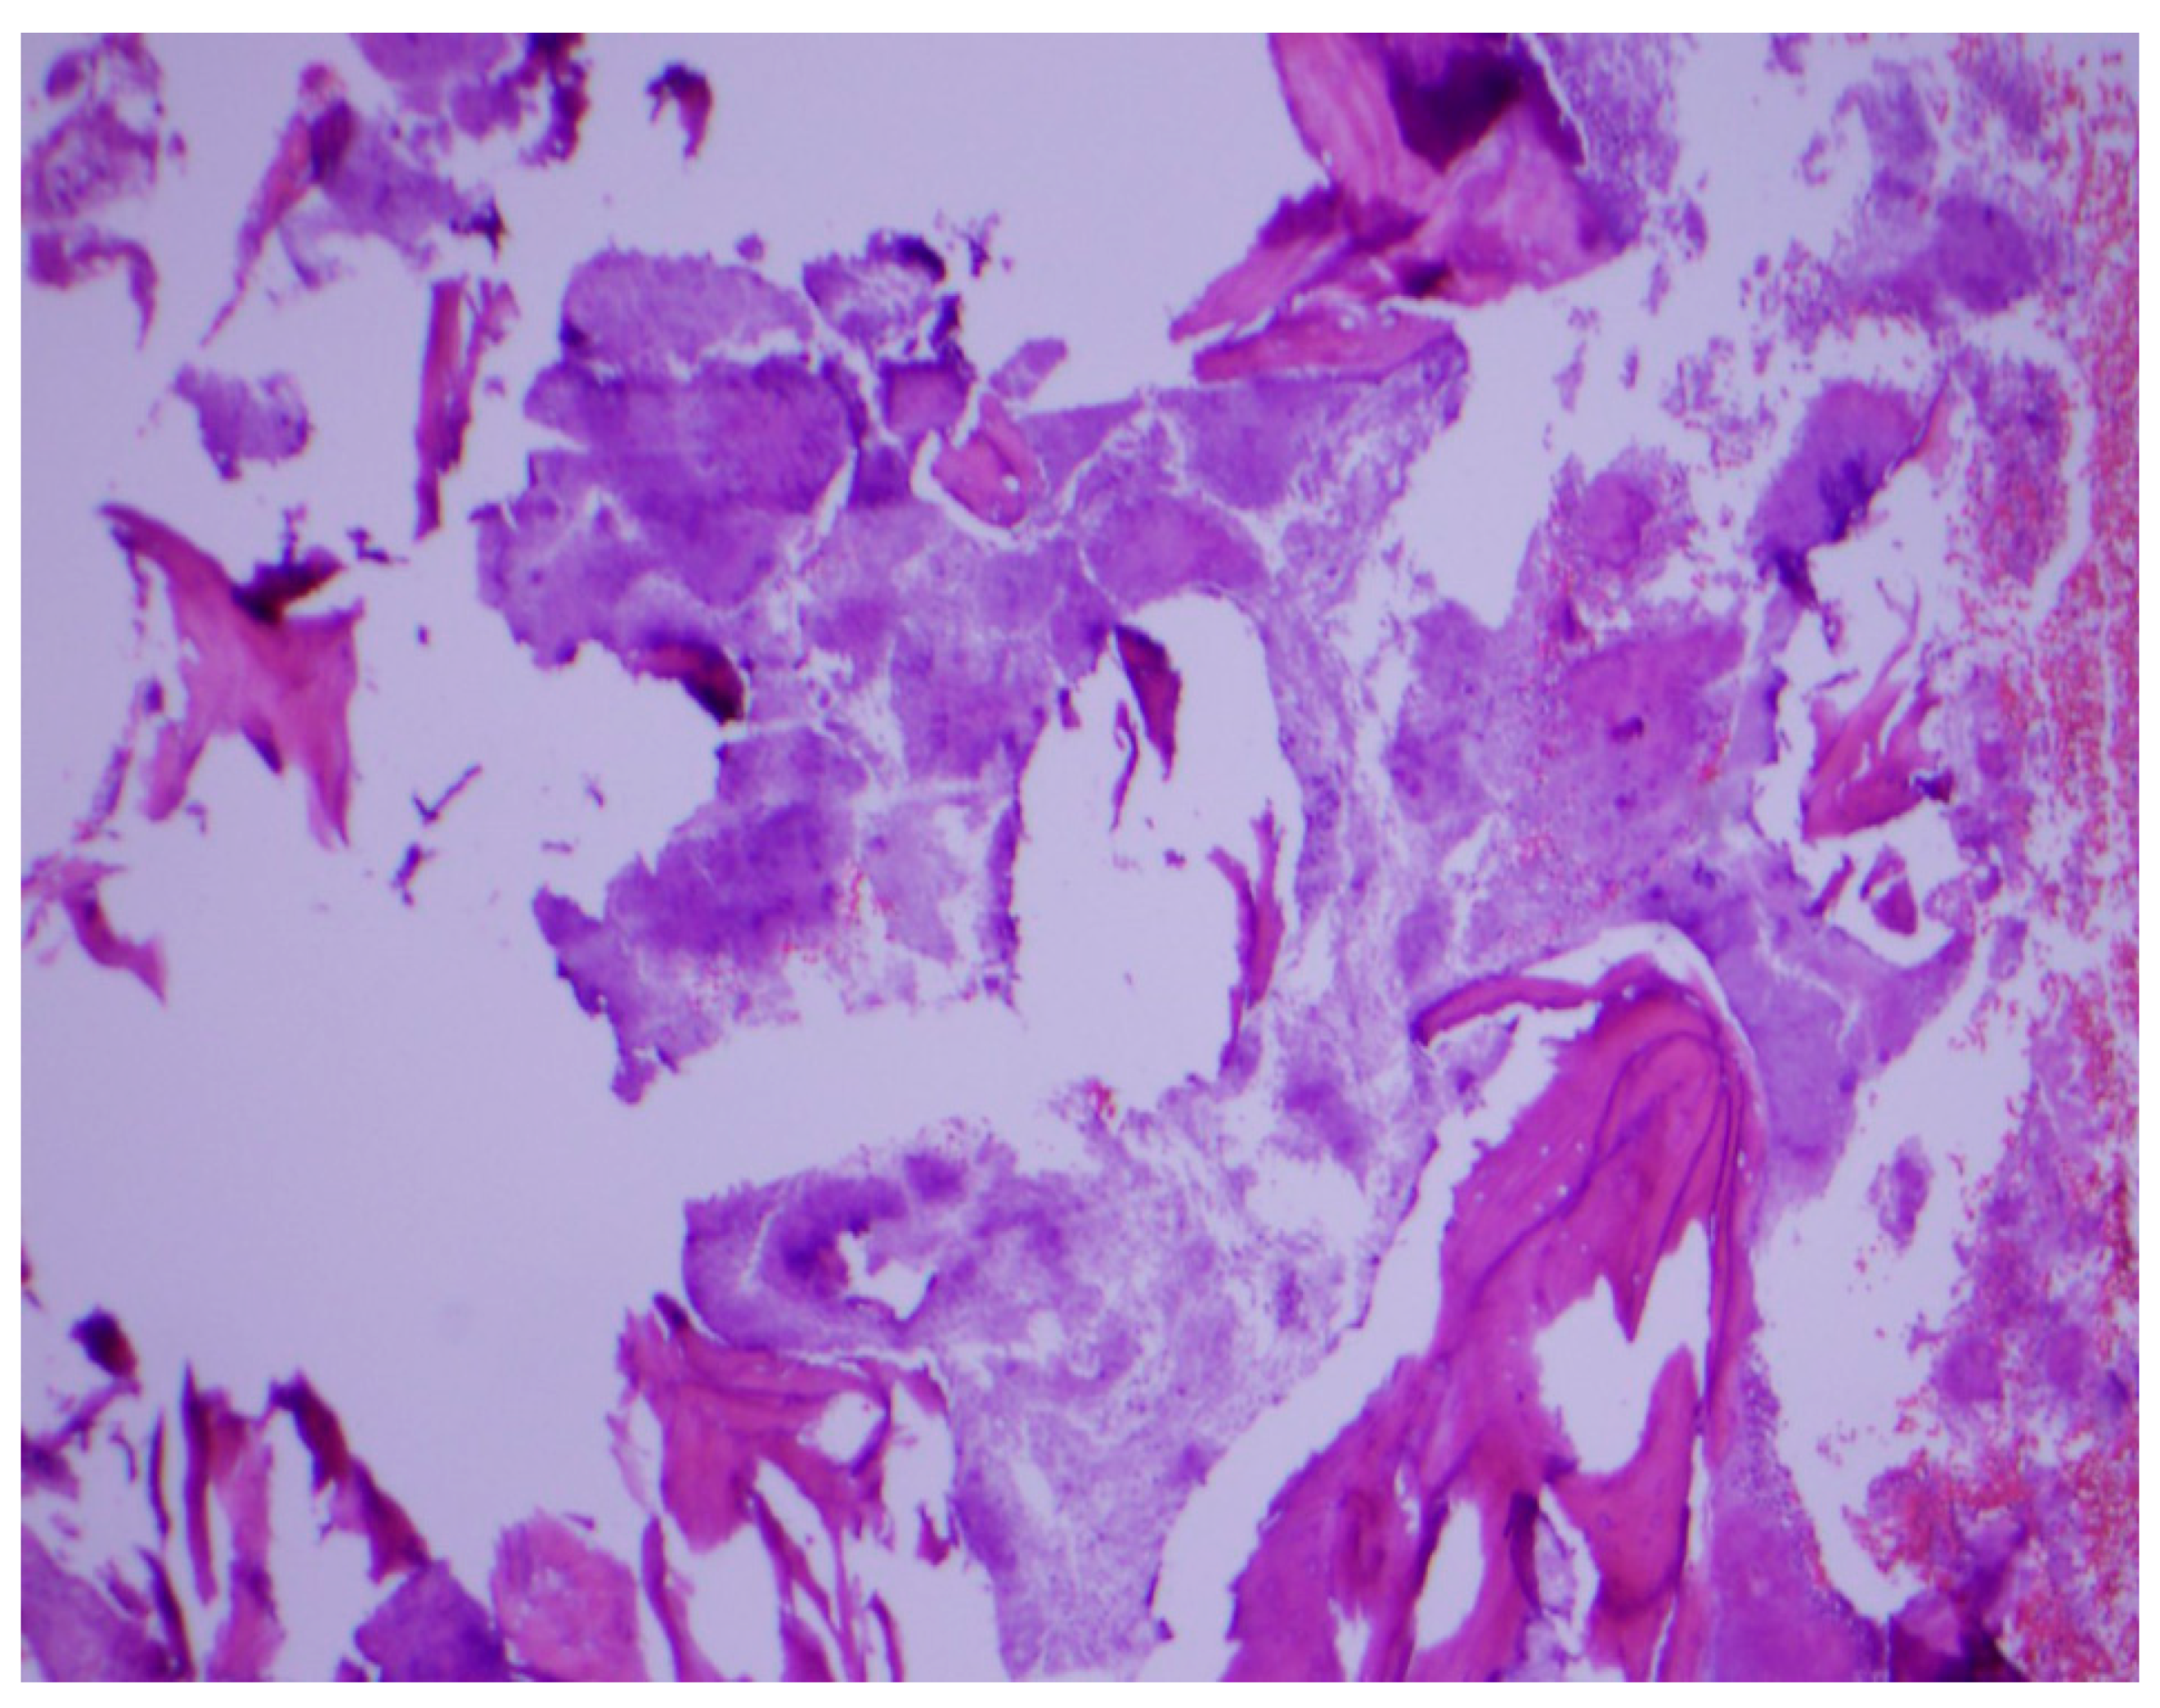

Histopathological examination of the mandibular bone showed osteonecrosis, sulfur granules and embedded organisms on hematoxylin and eosin (H&E) stain (Figure 3 and Figure 4), which were better characterized on Gomori-Grocott methenamine silver stain (GMS) as multiple branching organisms (Figure 5). The official histopathology report read, “acute and chronic osteomyelitis with Actinomyces-like organisms”. A diagnosis of actinomycosis was made, following which the patient was desensitized and treated with intravenous penicillin G for two weeks, followed by oral penicillin VK for six months. He made a complete recovery at the end of therapy with total resolution of symptoms and closure of the exposed bone.

Figure 3.

Osteonecrosis of the jaw on hematoxylin and eosin stain. Original magnification ×40.